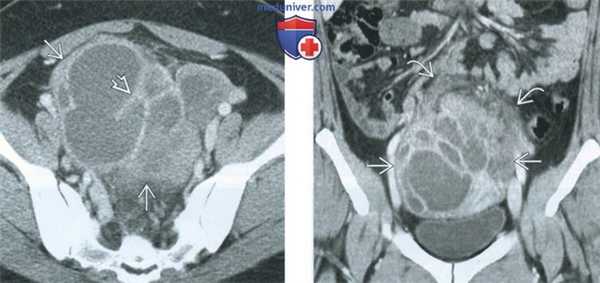

(Слева) Трансабдоминальная цветовая ультрасонография таза; определяется правый тубоовариальный абсцесс (ТОА) после расширения и выскабливания. В абсцессе отсутствует центральный цветовой поток. Эндометрий также утолщен.

(Справа) КТ с контрастированием, коронарный срез у той же пациентки; определяется распространение ТОА. Также визуализируется гиподенсивный эндометрий.

(Слева) При ТВУЗИ у пациентки с двусторонним тубоовариальным абсцессом в левых придатках визуализируется сложное солидно-кистозное образование. Аналогичная картина выявляется в правых придатках. Идентифицировать нормальные яичники не удается.

(Справа) При КТ с контрастным усилением в аксиальной плоскости у той же пациентки выявляются сложные объемные образования в придатках с обеих сторон с толстым ободком усиления и перегородками, накапливающими контрастное вещество, и центральной частью, имеющей низкую рентгеновскую плотность. Тазовая жировая клетчатка имеет тяжистый рисунок, обусловленный воспалительными изменениями, в малом тазу видны свободная жидкость и утолщение брюшины.